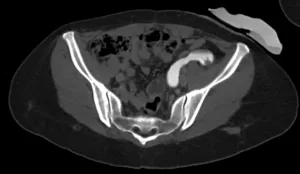

Fase nefrográfica

Fase excretora

Imagens-chave

Derivação urinária em alça delgada na fossa ilíaca à esquerda. Houve boa distensão da alça de derivação, porém nota-se falha de enchimento de aspecto polipoide na fase excretora medindo cerca de 2,2 x 1,0 cm. Sugere-se prosseguir investigação.

• Lesão polipoide na alça ileal da derivação urinária